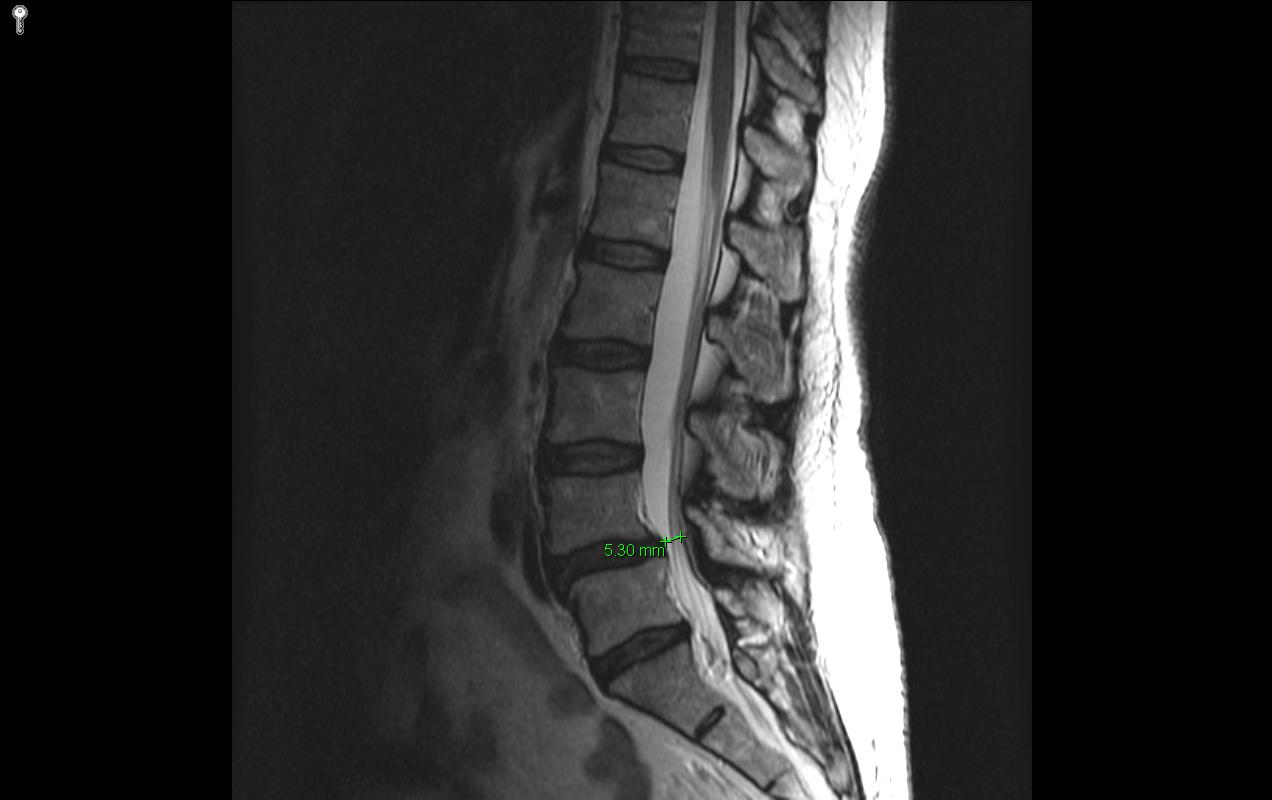

Purpose: Identify signs and symptoms indicative of lumbar spinal stenosis.